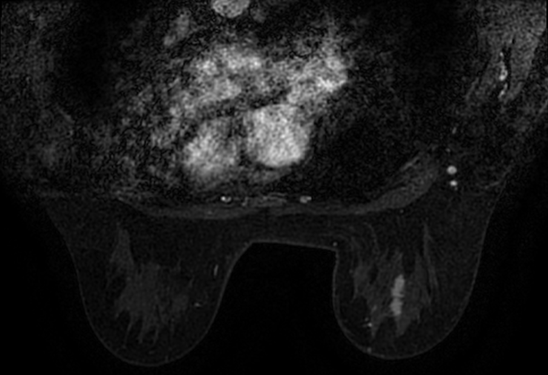

术前核磁共振图片